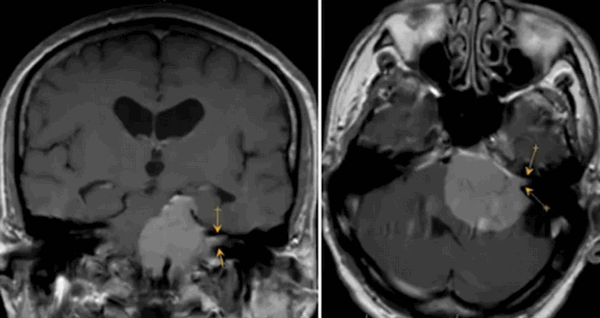

Опухоль мозжечка на МРТ (указана стрелкой)

Опухоли головного мозга долгое время диагностировали исключительно по клиническим признакам, часто слишком поздно. С появлением нейровизуализационных методов стало возможным выявление опасных патологий на ранних этапах их развития. Уже на первых стадиях формирования опухоль головного мозга на МРТ отчетливо видна, а врачи могут планировать дальнейшие действия. Ранняя диагностика увеличивает шансы на выздоровление даже при онкологических заболеваниях.

- опухоли мозжечка